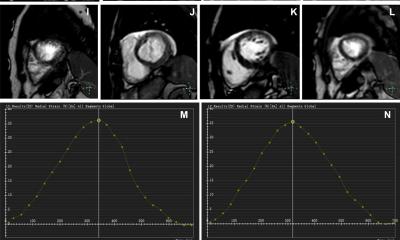

In the study, one of the first to observe the role of CMR in this setting, De Garate and Dastidar (Figure) compared the value of echocardiography and CMR in a cohort 231 acutely hospitalised patients. They found that CMR confirmed the echo diagnosis in 11% of these patients, but interestingly added significant new information in 41% and changed the diagnosis made on echo in 30% of the cases. ‘CMR is increasingly used in outpatients and our results now show the promising role of this technique in sicker hospitalised patients in whose diagnosis and management can be changed by having a CMR,’ Chiara Bucciarelli-Ducci, who directed the study, told European Hospital.

The study also compared the level of agreement between echocardiography and CMR in the assessment of left ventricular (LV) function. ‘We found that the level of agreement in patients with severe dysfunction was very good but in patients with mild and moderate dysfunction the agreement was only fair. ‘If the heart works normally or really badly the two techniques appear to perform equally well, but when there are mild-moderate abnormalities, CMR has the advantage of higher spatial resolution and can distinguish subtler abnormalities’, De Garate explained.